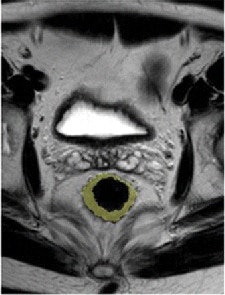

Pre- and post-treatment MRI was performed with a 1.5-tesla system (Intera R10, Philips Healthcare) using an eight-element pelvic phased-array surface coil. The subjects were imaged in the prone position after the placement of a thin rectal catheter in the rectum.

After initial localization imaging, researchers acquired MR images of the pelvis and rectum, with T2-weighted images obtained in the transverse, coronal, and sagittal planes during the scanning time of approximately 30 minutes.

The MR images calculated the mean tumor volume was 58 cm3 ± 75 before chemotherapy/radiation treatment and 20 cm3 ± 31 after therapy. The mean tumor volume reduction ratio in all patients was 68% ± 23.

Nougaret and colleagues also found that 25 of the 58 patients (43%) had a total volume reduction rate of at least 70%, while 33 individuals (57%) had a total volume reduction rate of less than 70%.

"A tumor volume reduction of at least 70% was significantly associated with good histologic regression (TRG 3 or 4) (P < .0001)," they added, "with an accuracy of 74% (43 of 58 patients), a positive predictive value of 88% (22 of 25 patients), and a negative predictive value of 64% (21 of 33 patients)."